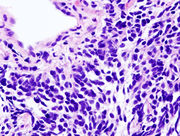

Malobuněčný typ karcinomu plic (mikroskopický pohled na střed po biopsii pomocí jehly).

Malobuněčný typ karcinomu plic (SCLC, zvaný také jako "karcinom ovesných buněk") je již méně častý. Má tendenci růst do horních cest dýchacích (primární a sekundární průduška) a roste rychle a do velkých rozměrů.[22] "Ovesná" buňka obsahuje hustou změť neurosekretních granulí (vezikuly obsahující neuroendokrinní hormony), který je s tímto endokrinním/paraneoplastickým syndromem spojen.[23] Zatímco zpočátku je citlivější k chemoterapii, v konečném důsledku přináší horší prognózy a ve výsledku končí metastátou. Malobuněčný karcinom plic je rozdělen do omezené fáze a rozšířené fáze onemocnění. Tento druh karcinomu plic je ostře spojován s kouřením.[24]